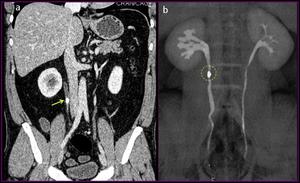

La URO-CT es una técnica diagnóstica optimizada para visualizar riñones, uréteres y vejiga mediante su examen con cortes finos (con TCMD), con la administración de contraste iodado y adquisición de imágenes en la fase excretora renal.

Vista coronal y post proceso en URO TC

Actualmente los TCMD (TAC con multidetector) permiten realizar estudios y obtener imágenes con alta resolución espacial y temporal, esto sumado a las reconstrucciones en tridimensionales (3D) y multiplanares de gran calidad han hecho que la URO-TC sea el estudio de elección en el diagnóstico de patología del tracto urinario, reemplazando a la urografía excretora (UIV)

Split Bolus en URO TC

En la actualidad ya se realiza el protocolo de UROTC-Split bolus de contraste, ya que implica menor dosis de radiación, este protocolo consiste en solo dos fases:

1. Fase sin contraste (baja dosis/dosis ultra baja)

2. Fase mixta nefrográfica-excretora.

Empleo de protocolo Split Bolus (Volumen sin contraste + Volumen con contraste)